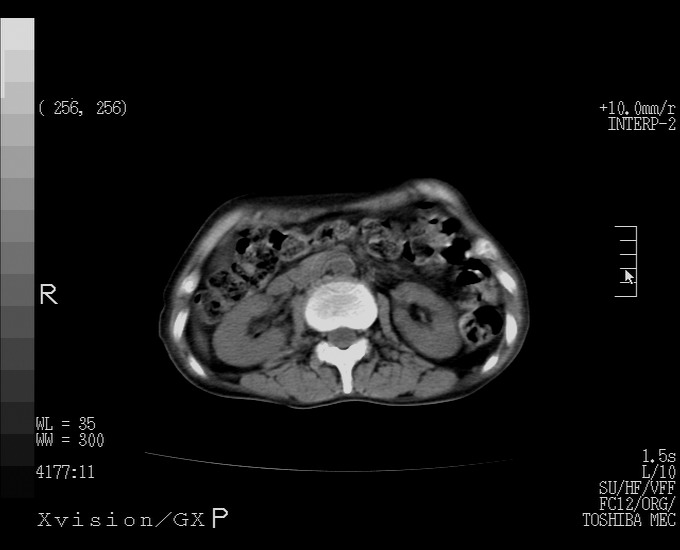

标题: CT25230:女,63岁,萎缩性胃炎病史,患者明显黄染,不能进 [打印本页]

标题: CT25230:女,63岁,萎缩性胃炎病史,患者明显黄染,不能进

怎么没有增强呢?胆囊那么大,密度有些高啊。

慢性胆囊炎,胆囊占位不排除,建议增强或彩超。

考虑胆囊炎 不除外泥沙样结石

胆囊体积增大,胃窦壁增厚

胆囊体积增大,密度不均匀,结石不除外;胃壁增厚,考虑胃癌,建议增强。

胆囊体积增大,密度增高,较均匀,外缘也较光滑,应考虑胆囊炎。因为胃未充盈,不好说壁增厚。肝左叶及脾门处见低密度灶,有可能是血管瘤,不排除囊肿。建议超声检查或强化。

这就是江湖人称的“内科黄疸”, 肝内胆汁淤积症(ic)?